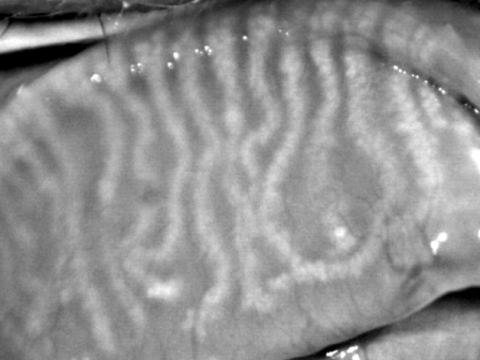

H πρεσβυωπία οφείλεται στη φθορά (με την γήρανση) του φυσικού φακού του οφθαλμού και ελάττωση της προσαρμοστικότητας (ικανότητα προσαρμογής εστίασης) του στις κοντινές αποστάσεις. Ο φακός χάνει την ελαστικότητά του και από μαλακός και εύκαμπτος γίνεται σκληρός και άκαμπτος, χάνοντας την ικανότητα να αλλάζει καμπυλότητα και να εστιάζει στις κοντινές αποστάσεις. Επιπροσθέτως ο μυς στον οποίο στηρίζεται ο φακός (ακτινωτός μυς) εμφανίζει μια προοδευτική ατροφία λόγω γήρανσης.